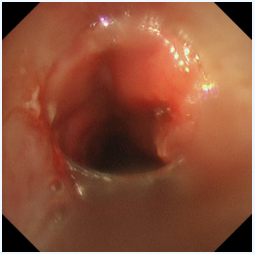

患者王先生(化名),20多年前因喉癌接受了喉切開手術(shù),長(zhǎng)期留置氣管套管。一周前,他再次感受到熟悉的窒息感——呼吸困難加劇,喉間痰鳴,卻有痰咳不出,每一次吸氣都異常費(fèi)力,家人緊急將他送至瑞康醫(yī)院救治。經(jīng)檢查,王先生的氣道出現(xiàn)了嚴(yán)重的增生性狹窄。新生的肉芽組織像藤蔓一樣在主氣道內(nèi)生長(zhǎng),使得原本就不寬敞的呼吸道變得更加狹窄,最嚴(yán)重處堵塞程度超過50%。這不僅是導(dǎo)致他呼吸困難的直接原因,也使得分泌物無(wú)法排出,易引發(fā)肺部感染和呼吸衰竭,情況萬(wàn)分危急。

激光灼蝕,精準(zhǔn)“開路”:在氣管鏡引導(dǎo)下,首先利用高頻激光對(duì)堵塞氣道的增生組織進(jìn)行精準(zhǔn)、迅速地汽化切割。激光如同一位技藝高超的“雕刻師”,快速清除掉大部分梗阻物,為后續(xù)治療打開一個(gè)通暢的“窗口”,迅速緩解患者的窒息風(fēng)險(xiǎn)。